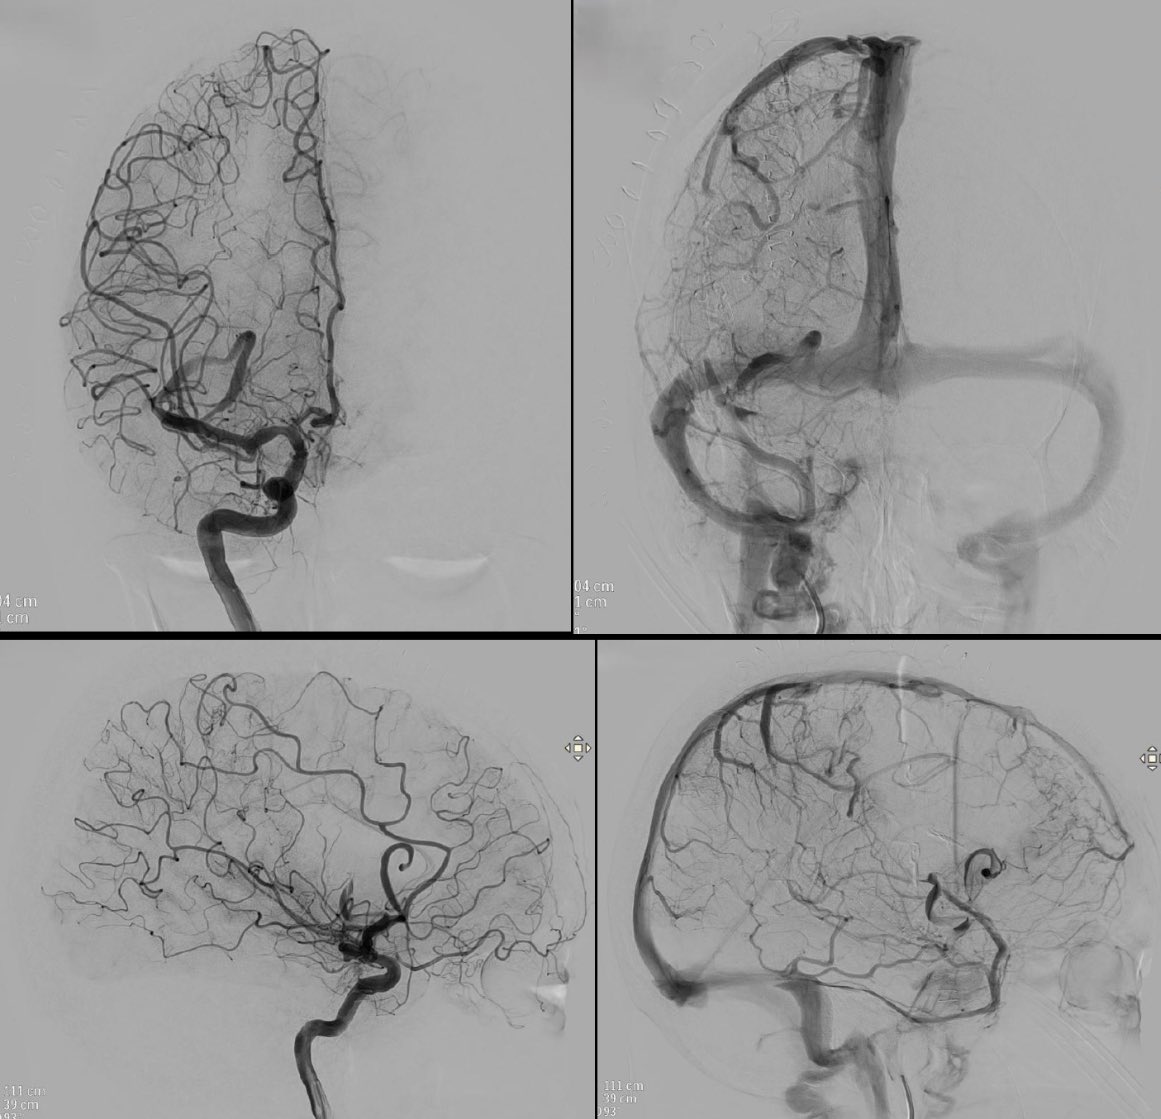

Distal occlusion in right PCA recanalized using 3Max (@PenumbraEMEA). In my opinion aspiration should be the first option in distal occlusions (let's wait for randomized trials stent versus aspiration in DMVOs).